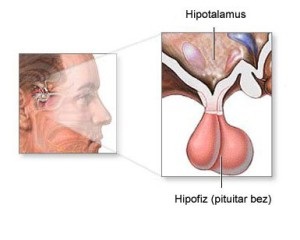

Glanda pituitară - un cheag de tesut cam de marimea unui bob de mazare, situat aproape exact în centrul capului, la baza creierului și chiar în spatele rădăcina nasului. Ea atârnă sub creier este ca o cireașă agățat pe o ramură de copac. Glanda pituitara este o culoare gri-galben. Si femeile glanda pituitara este de obicei mai mult.

Cu toate acestea, ca o glanda endocrina suprem, glanda pituitara în sine este subiect al sistemului nervos central, in special hipotalamus. Ca glanda pineala, glanda pituitara este o parte a dezvoltării umane Trinity, care este condus de către hipotalamus.